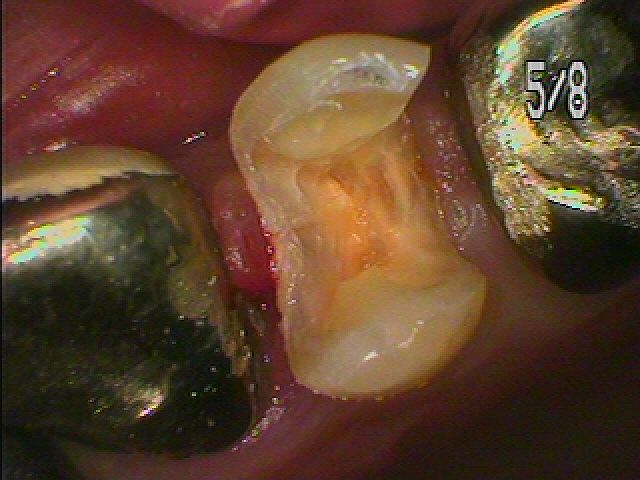

左上4番の銀歯外して虫歯治療 この銀歯の下に虫歯が存在しています|お知らせ |広島市安佐南区の歯科医院 左上4番の銀歯外して虫歯治療 この銀歯の下に虫歯が存在しています トップ お知らせ・ブログ お知らせ 左上4番の銀歯外して虫歯治療 この銀歯の下に虫歯が存在しています 左上4番の銀歯外して虫歯治療 この銀歯の下に虫歯が存在しています この銀歯を外していきます 銀歯を外していきました 下はこのように大きく虫歯になっています 中も虫歯が蔓延しています 神経に気を付けながら虫歯を除去していきました CR樹脂にて覆罩を行い型取りを行っていきます セレックセラミックにて白くきれいに仕上がりました このように本来の歯のようにきれいに仕上がりました 喜んでいただきました Web診療予約 初めての方へ 選ばれ続ける理由 院内設備について 歯が痛いしみる一般歯科 歯がぐらぐらする歯周病 健康な歯を保ちたい予防歯科 子供の虫歯予防をしたい小児歯科 銀歯をセラミックに審美歯科 白い歯を目指しませんか?ホワイトニング 矯正専門医がいるので安心矯正歯科 抜けた歯を補いたいインプラント・入れ歯 医院案内 スタッフ紹介 メリィハウス歯科クリニックオフィシャルホームページ ラベンダー歯科クリニックオフィシャルホームページ お知らせ・ブログ ホーム 診療科目 一般歯科 歯周病治療 予防治療 小児歯科 審美治療 ホワイトニング 矯正歯科 入れ歯・インプラント マウスピース矯正 初めての方へ 院長・スタッフ 設備紹介 医院案内・アクセス メニューを閉じる